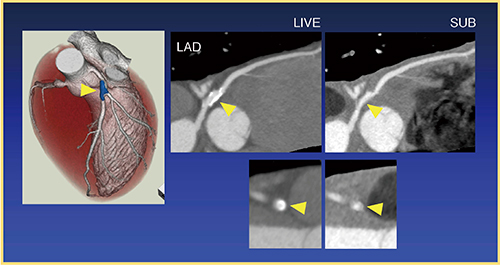

図3はRealPrep法で撮影したサブトラクションCT画像であるが,左前下行枝(LAD)の基部の大きな石灰化が除去され,内腔がよく観察できる。RealPrep法は冠動脈のサブトラクションCTにおいて,最も成功率の高い撮影法だと言える。

図3 1呼吸法(RealPrep法)での冠動脈サブトラクション